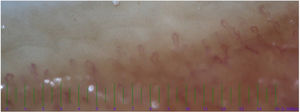

The nailfold capillaroscopy was conducted on both the KD and control groups. The abnormal capillaroscopic diameter was identified in 21 patients from KD group and four patients in the control group (Table 2). The most common abnormality in the evaluation of capillaries diameter was irregular dilatation (Fig. 1) seen in 11 (35.4%) KD patients and 4 (13.3%) in the control group. The normal capillary architecture distortions were commonly seen in KD group (n=8). On the other hand, there were no findings of architectural capillary abnormality in the control group (P=0.003). About half of KD patients had a reduction in capillary density (Fig. 2), while no similar abnormality was observed in the control group (P<0.001). There was no significant difference between KD patients and the control group in terms of morphology variations (P=0.4). Moreover, a positive correlation was observed between coronary involvement and abnormal capillaroscopic results (r=0.65, P<0.03).